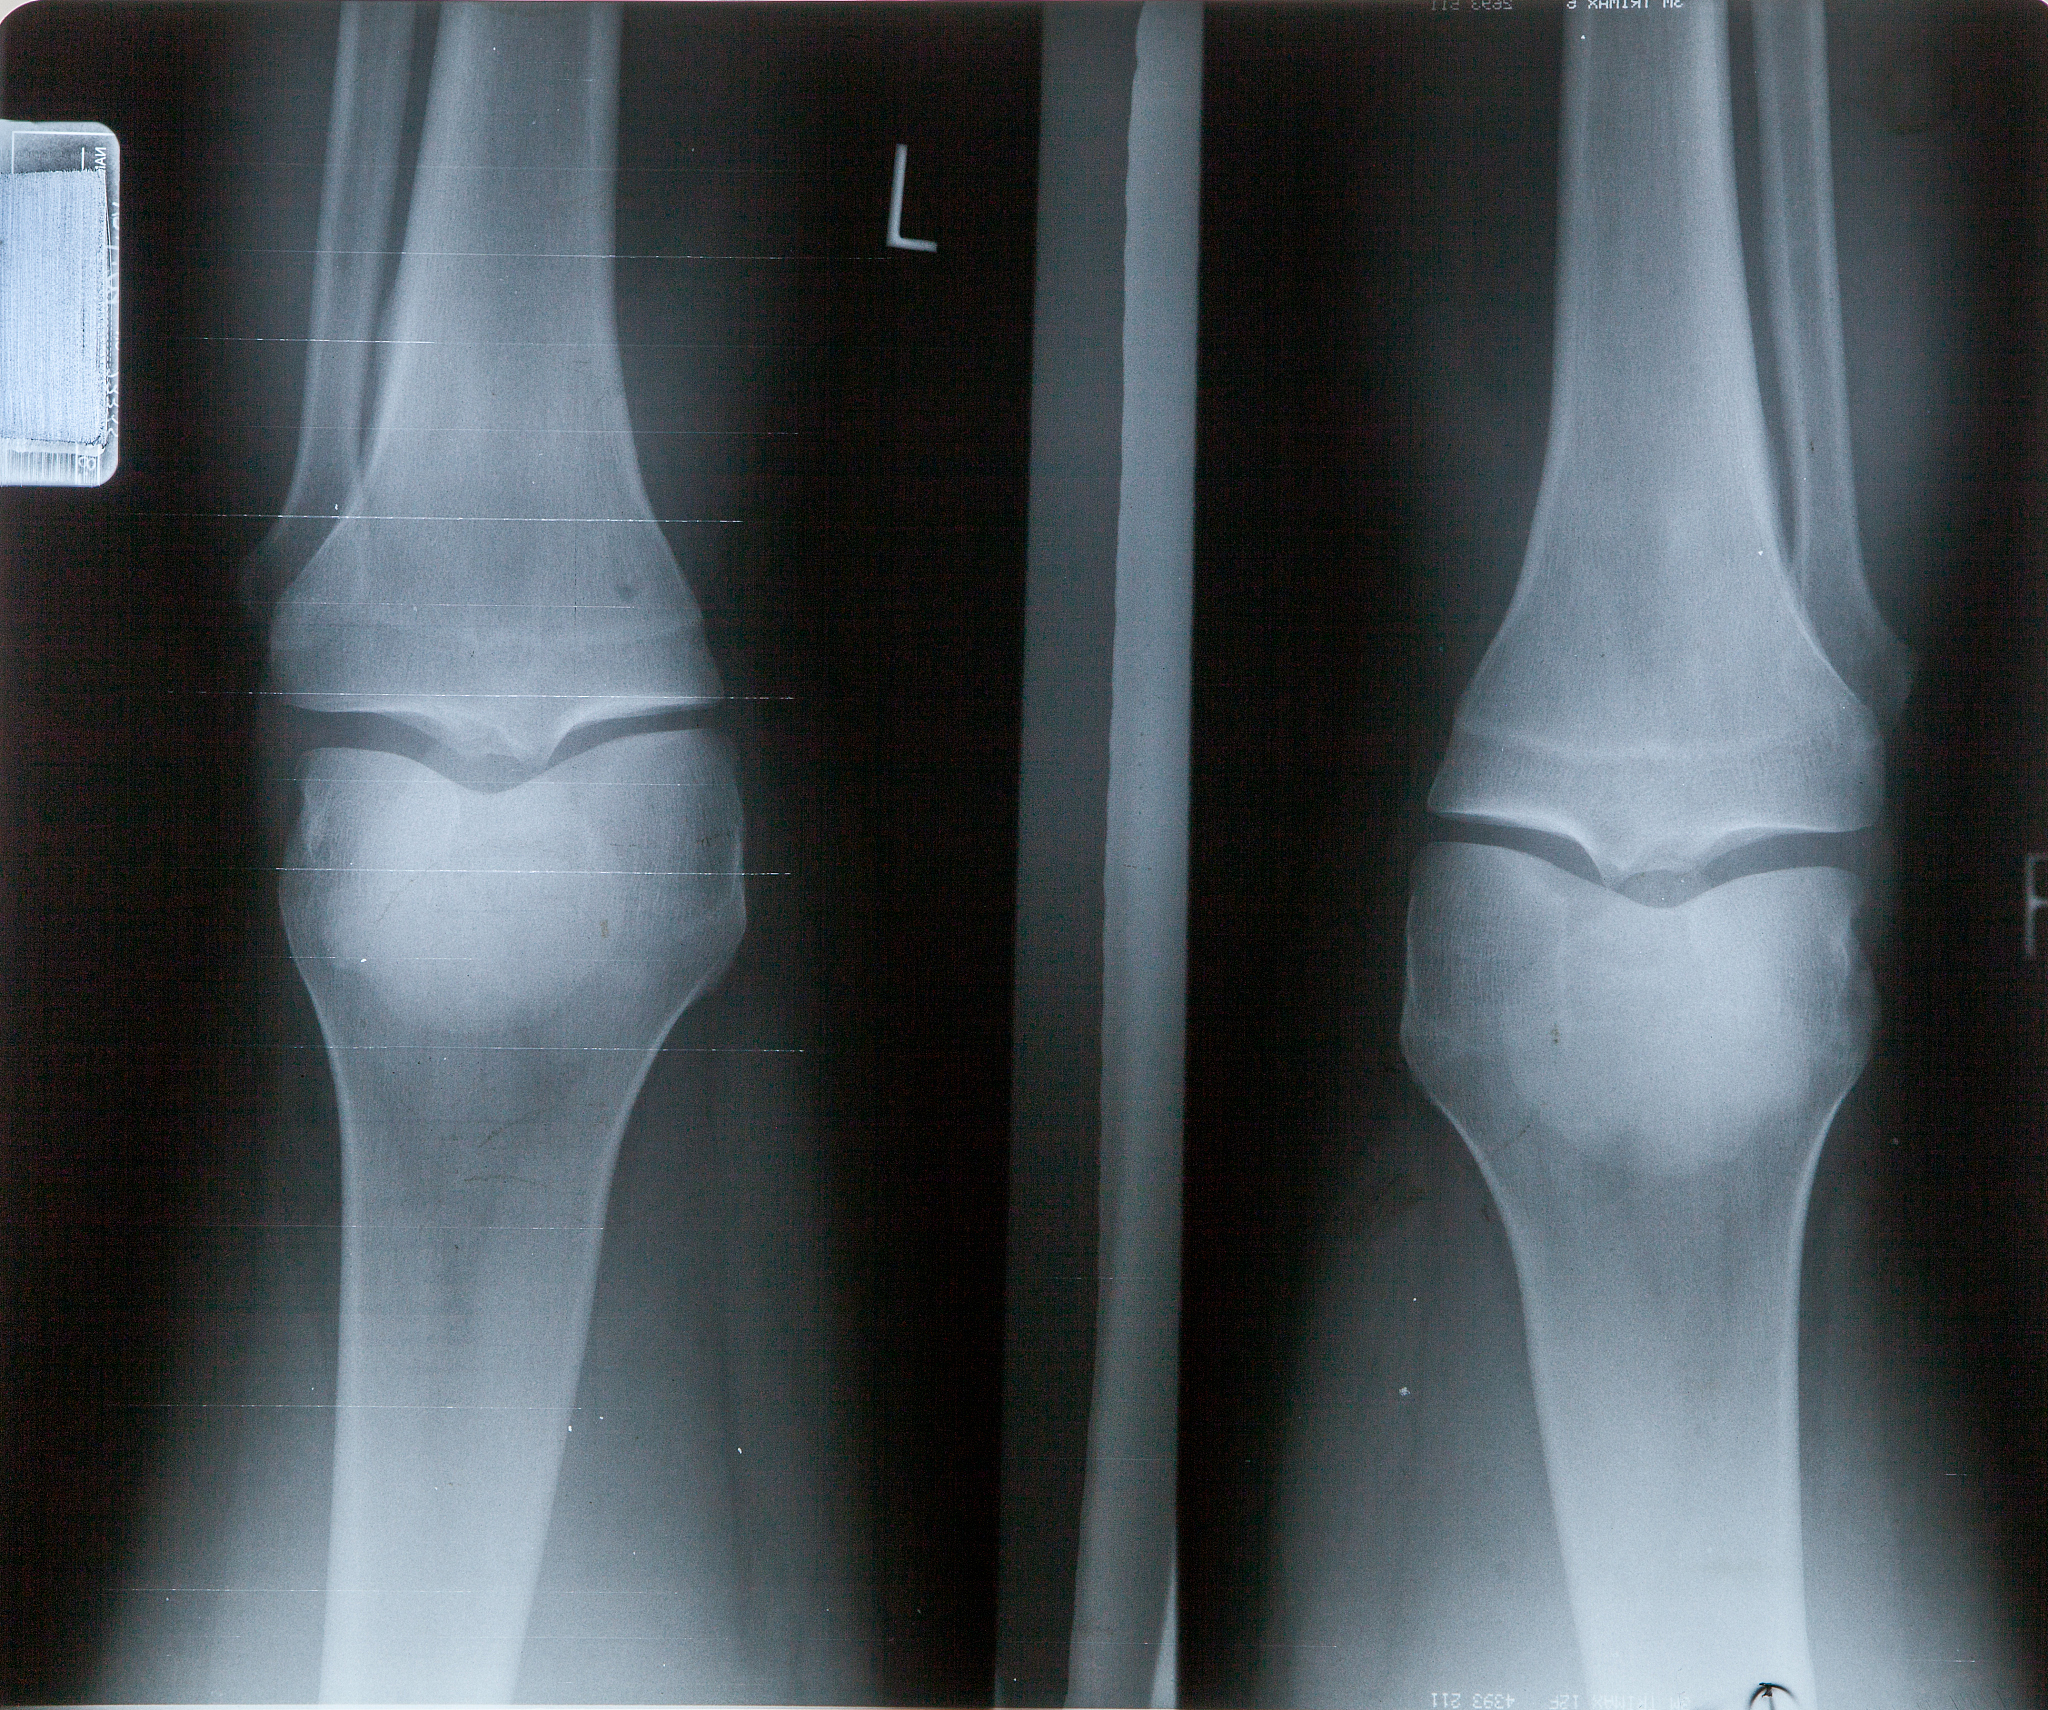

如果出现这种情况,建议及时就医,进行详细的检查和诊断。医生可能会建议进行X光、MRI或关节镜检查,以确定具体的病因和治疗方案。治疗滑囊炎的方法通常包括休息、物理治疗、药物治疗和手术等。